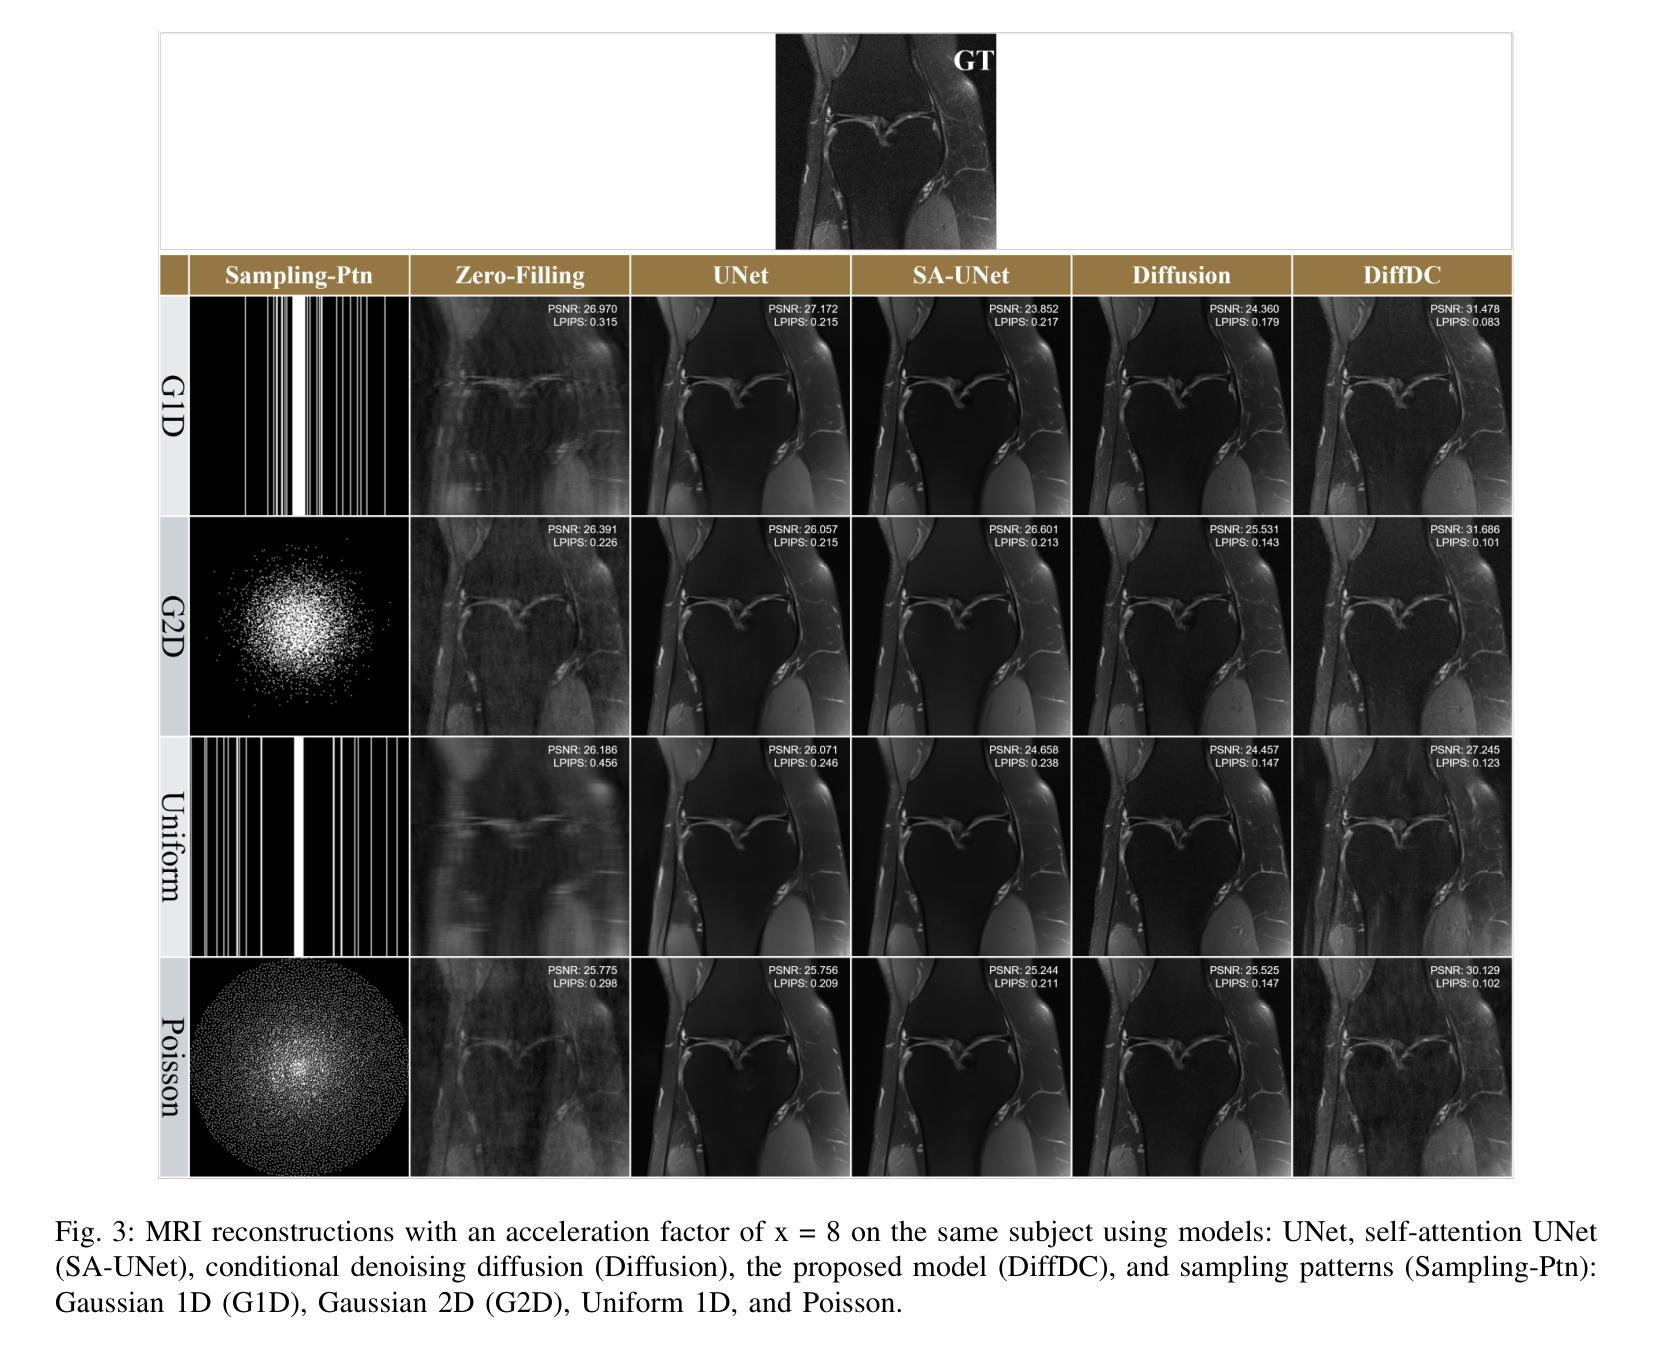

Conditional Denoising Diffusion Model-Based Robust MR Image Reconstruction from Highly Undersampled Data

Magnetic Resonance Imaging (MRI) is a critical tool in modern medical diagnostics, yet its prolonged acquisition time remains a critical limitation, especially in time-sensitive clinical scenarios. While undersampling strategies can accelerate image acquisition, they often result in image artifacts and degraded quality. Recent diffusion models have shown promise for reconstructing high-fidelity images from undersampled data by learning powerful image priors; however, most existing approaches either (i) rely on unsupervised score functions without paired supervision or (ii) apply data consistency only as a post-processing step. In this work, we introduce a conditional denoising diffusion framework with iterative data-consistency correction, which differs from prior methods by embedding the measurement model directly into every reverse diffusion step and training the model on paired undersampled-ground truth data. This hybrid design bridges generative flexibility with explicit enforcement of MRI physics. Experiments on the fastMRI dataset demonstrate that our framework consistently outperforms recent state-of-the-art deep learning and diffusion-based methods in SSIM, PSNR, and LPIPS, with LPIPS capturing perceptual improvements more faithfully. These results demonstrate that integrating conditional supervision with iterative consistency updates yields substantial improvements in both pixel-level fidelity and perceptual realism, establishing a principled and practical advance toward robust, accelerated MRI reconstruction.

磁共振成像(MRI)是现代医学诊断中的重要工具,但其漫长的采集时间仍然是一个关键的限制,特别是在时间敏感的临床场景中。尽管欠采样策略可以加速图像采集,但它们通常会导致图像出现伪影和质量下降。最近的扩散模型显示出通过学习强大的图像先验知识从欠采样数据中重建高保真图像的潜力;然而,大多数现有方法要么(i)依赖无配对监督的无监督分数函数,要么(ii)仅将数据一致性作为后处理步骤应用。在这项工作中,我们引入了一个具有迭代数据一致性校正的条件去噪扩散框架,它与先前的方法的不同之处在于,它将测量模型直接嵌入到每个反向扩散步骤中,并在配对欠采样-真实数据上训练模型。这种混合设计结合了生成灵活性和MRI物理的显式实施。在fastMRI数据集上的实验表明,我们的框架在结构相似性度量(SSIM)、峰值信噪比(PSNR)和局部感知图像感知相似性(LPIPS)上始终优于最新的深度学习和扩散方法,LPIPS更真实地捕捉到了感知改进。这些结果表明,将条件监督与迭代一致性更新相结合,在像素级保真度和感知真实性方面都取得了显著改进,为实现稳健、加速的MRI重建提供了有原则和实际进步的突破。

Summary

本文介绍了利用扩散模型加速磁共振成像(MRI)的技术。传统的MRI采集时间较长,而扩散模型能够在保证图像质量的同时,通过学习方法加速图像采集。本文提出了一种结合条件去噪扩散框架和迭代数据一致性校正的新方法,将测量模型直接嵌入到每个反向扩散步骤中,并在配对欠采样-真实数据上进行训练。实验证明,该方法在SSIM、PSNR和LPIPS等指标上均优于最新的深度学习和扩散方法,尤其在感知改善方面表现更出色。